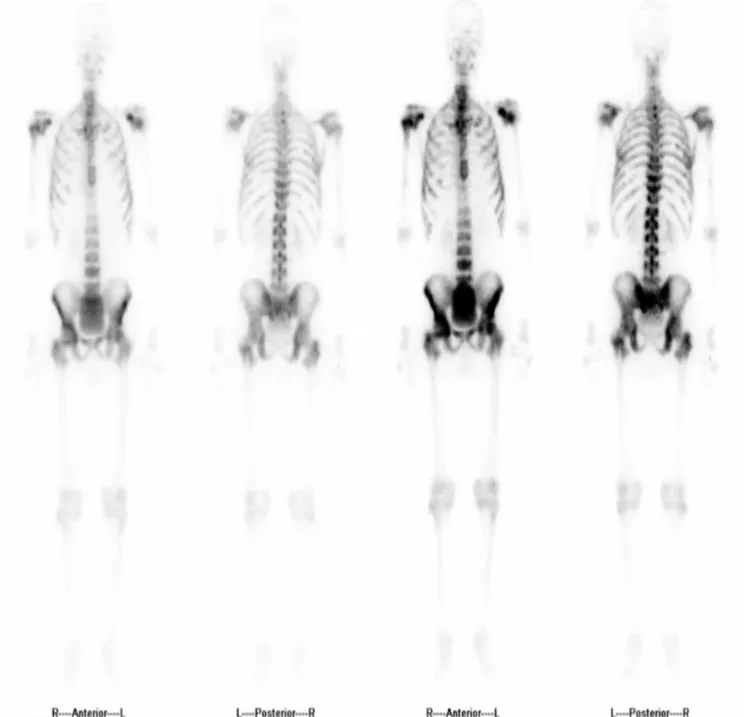

骨扫描 (2025-6-4)

全身广泛多发骨转移。